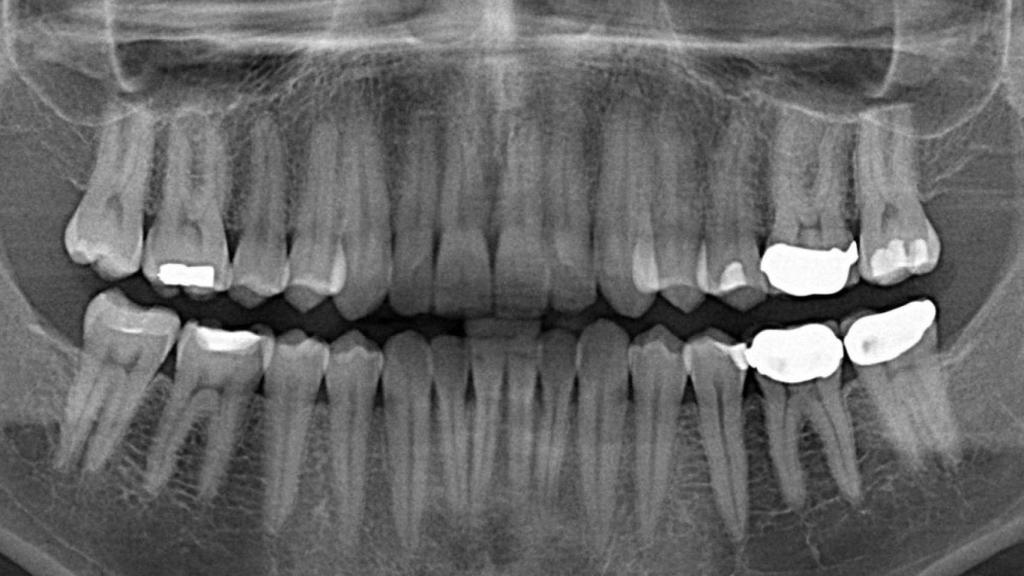

Como sabéis, cuando un diente queda dañado por una caries o algún otro tipo de lesión, tenemos varias opciones. Entre ellas, las endodoncias (de los cuales entre el 10-15% fallan) o directamente la retirada de los dientes y la colocación de un implante dental artificial en su lugar. Como imaginaréis, esta última opción es la más cara de todas.

Un biomaterial de células madre, el fin de las endodoncias

Con todos estos datos en mente, Adam Celiz y sus colegas de especialistas en biomateriales terapéuticos de la Universidad de Nottingham han intentado buscar un buen sustituto a las técnicas actuales de endodoncia donde se quita la pulpa del diente y el tejido blando (el cual contiene vasos sanguíneos, nervios y otros tejidos), un tratamiento que acaba debilitando la base del diente y que, en ocasiones, implica que la pieza dentaria necesite ser retirada.

Su método consiste en el uso de un biomaterial sintético que estimula el crecimiento de las células madre en la pulpa del diente. De la misma forma que los biomateriales usados actualmente tan solo como relleno, este material basado en células madre también se inyecta directamente en el diente y se endurece con luz ultravioleta.

En las pruebas in vitro de laboratorio, este biomaterial de células madre ha conseguido estimular la proliferación y diferenciación de dichas células en la dentina, el tejido óseo que forma la mayor parte del diente justo por debajo del esmalte blanco. Según los investigadores, usando este tipo de relleno en un diente dañado se podría reparar el diente sin acabar debilitándolo o incluso sustituyéndolo por un implante dental como sucede hoy en día.

Celiz opina que, en un futuro cercano, todas las endodoncias podrían basarse en este biomaterial de células madre como tratamiento para reparar los dientes dañados, los cuales serían capaces de curarse a sí mismos reduciendo la tasa de fracaso de los empastes actuales, e incluso eliminar la necesidad de acabar con las raíces dentarias.